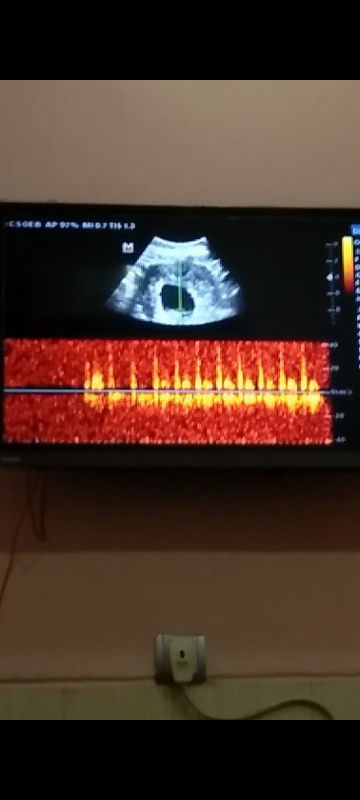

Tentang USG

Bun aku mau tanya, Usia kandungan aku 24Weeks Kira-kira kalo aku USG udah kelihatan JK nya belom ya Bun?? Terakhir USG aku usia kandungan 3Bulan Bun..

Bun mau tanya , Kemarin saya USG tgl 27 usia kandungan sudah 10Week tp kenapa ya baru kelihatan kantong nya saja tapi sudah terlihat detak Jantung nya.. Saya kehamilan pertama kurang paham siapa tau bunda bunda ada yg bisa Bantu Jawab?🙏#seriusnanya #bantusharing